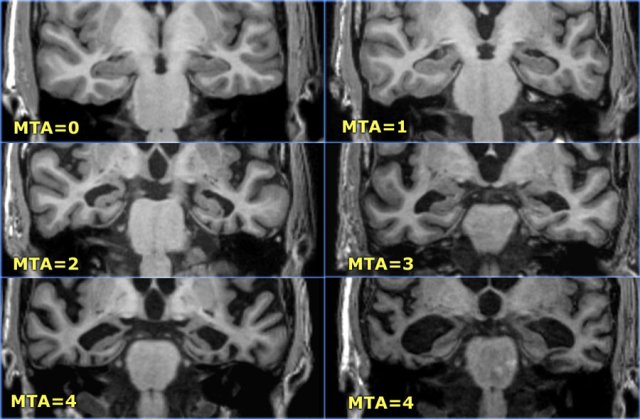

MTA-scale for Medial Temporal lobe Atrophy

The MTA-score should be rated on coronal T1-weighted images at a consistent slice position.

Select a slice through the corpus of the hippocampus, at the level of the anterior pons.

> 75 years : MTA-score 3 or more is abnormal (i.e. 2 can still be normal at this age)

Data from a study with 222 controls and patients with various forms of dementia in which this visual rating scale was used to assess temporal lobe atrophy suggest that sensitivities and specificities of 85% can be obtained for patients with AD.

The score is based on a visual rating of the width of the choroid fissure, the width of the temporal horn, and the height of the hippocampal formation.

- score 0: no atrophy

- score 1: only widening of choroid fissure

- score 2: also widening of temporal horn of lateral ventricle

- score 3: moderate loss of hippocampal volume (decrease in height)

- score 4: severe volume loss of hippocampus

< 75 years: score 2 or more is abnormal.

> 75 years: score 3 or more is abnormal.

Here you can scroll through the images for examples of MTA score 0-4.

A high MTA-score is very sensitive for the diagnosis of Alzheimer disease and is present in the vast majority of patients with AD, while in controls a positive score is almost always absent (table on the left).

Therefore it is a good test to discern controls from patients with AD.

This test is not completely specific for AD however, as MTA can also be found in other forms of dementias (7).

On the other hand if a patient with mild cognitive impairment (MCI) a possible 'prodromal state of AD' has a negative MTA-score, it is very unlikely that this patient will develop AD (high sensitivity yields high negative predictive value), except in very young subjects, in whom a more posterior pattern of atrophy can be observed in AD.